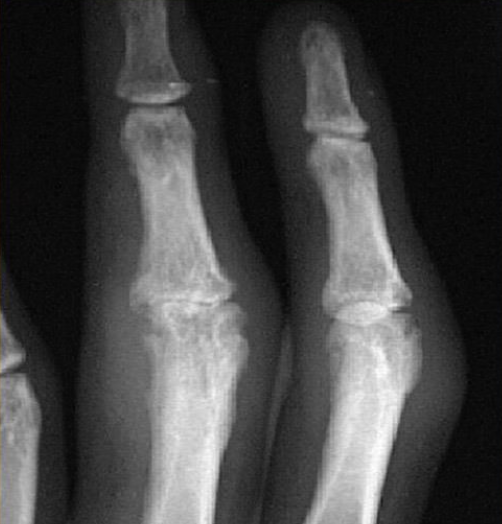

Name 2 radiological abnormalities?

a. Erosion of proximal interpharyngeal joint

b. Swelling of the in the middle finger

c. sublaxation of the joints -

What is likely etiology of arthritis

a. rheumatoid arthritis -

Which blood test will you do for diagnosis?

ACPA , RF